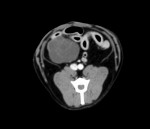

症例29 10歳 柴犬

エコー検査で腹腔内に直径5cm大の腫瘤を認めたため、CT検査を実施。

腫瘤は卵巣で周囲の臓器への癒着は認められなかったため、そのまま子宮および卵巣の摘出を行なった。

腹腔内の腫瘤には様々な可能性があるため、摘出可能かどうか判断するためにCT検査が有用である。